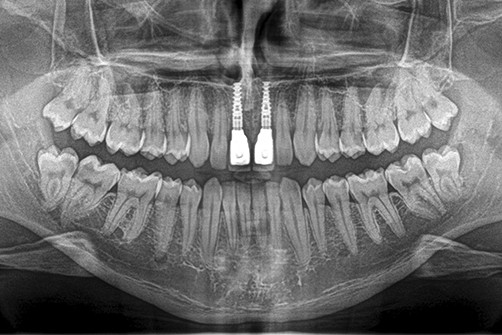

Umożliwia on wykonanie zdjęć panoramicznych – OPG, które uwzględniają obraz całości kości szczęk i żuchwy, całego uzębienia oraz pozostałych szczegółów anatomicznych takich jak zatoki szczękowe, nos, stawy skroniowo żuchwowe oraz oczodoły

Obraz diagnostyczny przedstawiany jest w dwóch wymiarach co ogranicza przestrzenną analizę interesującego nasz obszaru anatomii pacjenta. Zdjęcie panoramiczna w połączeniu z klinicznym badaniem jamy ustnej pacjenta daje pełną, podstawową informację odnośnie diagnozowanego obszaru.

Zdjęcie pantomograficzne, zwane również panoramicznym, to specjalistyczne badanie obrazowe używane do celów stomatologicznych. Wykonujemy je, gdy istnieje potrzeba zobrazowania wszystkich zębów szczęki i żuchwy (również tych zatrzymanych), zatok szczękowych, stawów skroniowo-żuchwowych, a także otaczających tkanek.

Wykonujemy je, ustawiając pacjenta przed kolumną aparatu, następnie polecamy, aby zagryzł specjalny ustnik, przez co uzyskujemy właściwą pozycję głowy, która gwarantuje odpowiednią projekcję. Podczas badania należy przez kilka sekund zachować bezruch oraz wykonywać polecenia technika. W trakcie badania głowica pantomografu krąży wokół głowy pacjenta przez kilka sekund, a uzyskany obraz jest od razu widoczny na monitorze.